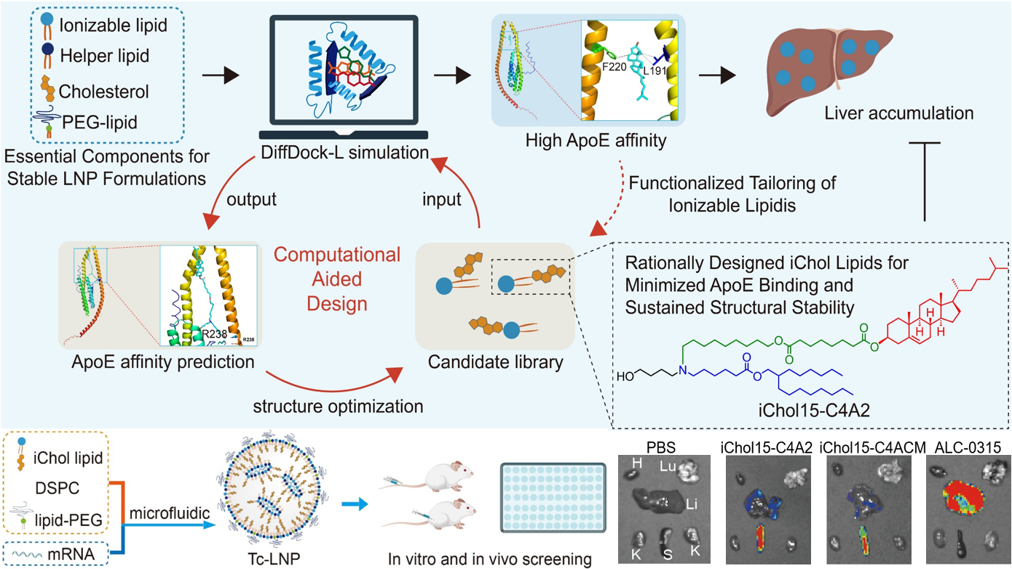

脂质理性设计

采用组合化学策略,基于可电离氨基、 疏水尾链及连接键的模块化设计,并引入人工智能(AI) 和创新化学合成方法,合成多功能脂质分子文库;制备具有高 RNA 包封率的脂质纳米颗粒(LNP),通过结构优化调控 LNP 与生物体系的相互作用,实现安全高效 LNP 或低肝富集型 LNP 等 RNA 载体文库的高效构建与筛选。

代表性论文:Journal of the American Chemical Society, 2025; ACS Nano, 2024; ACS Nano, 2022